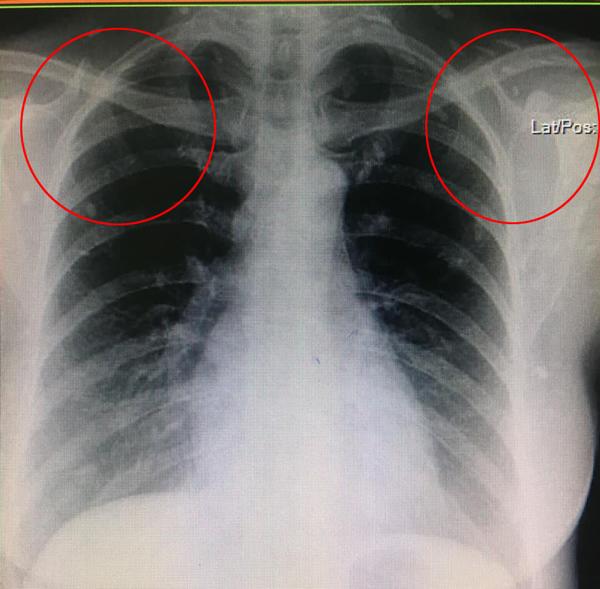

Sau khi chụp X-quang, thấy khắp cơ thể đặc biệt đầy những đốm trắng lạ kỳ. Bác sĩ khi nhìn vào cũng vô cùng kinh ngạc và cho biết đây là những ký sinh trùng đang nằm trên khắp cơ thể nữ bệnh nhân, đặc biệt là phần chân.

Bác sĩ cũng cảnh báo nếu toàn bộ ký sinh trùng này không được loại bỏ thì chỉ một thời gian ngắn nữa, nó có thể gây suy hô hấp hoặc thậm chí tử vong.

Loại ký sinh trùng này được xác định là ấu trùng của sán dải heo hay sán dải lợn. Những nang ấu trùng nhiễm vào não, cơ hoặc các mô khác có thể gây ra các cơn động kinh khởi phát tuổi trưởng thành.